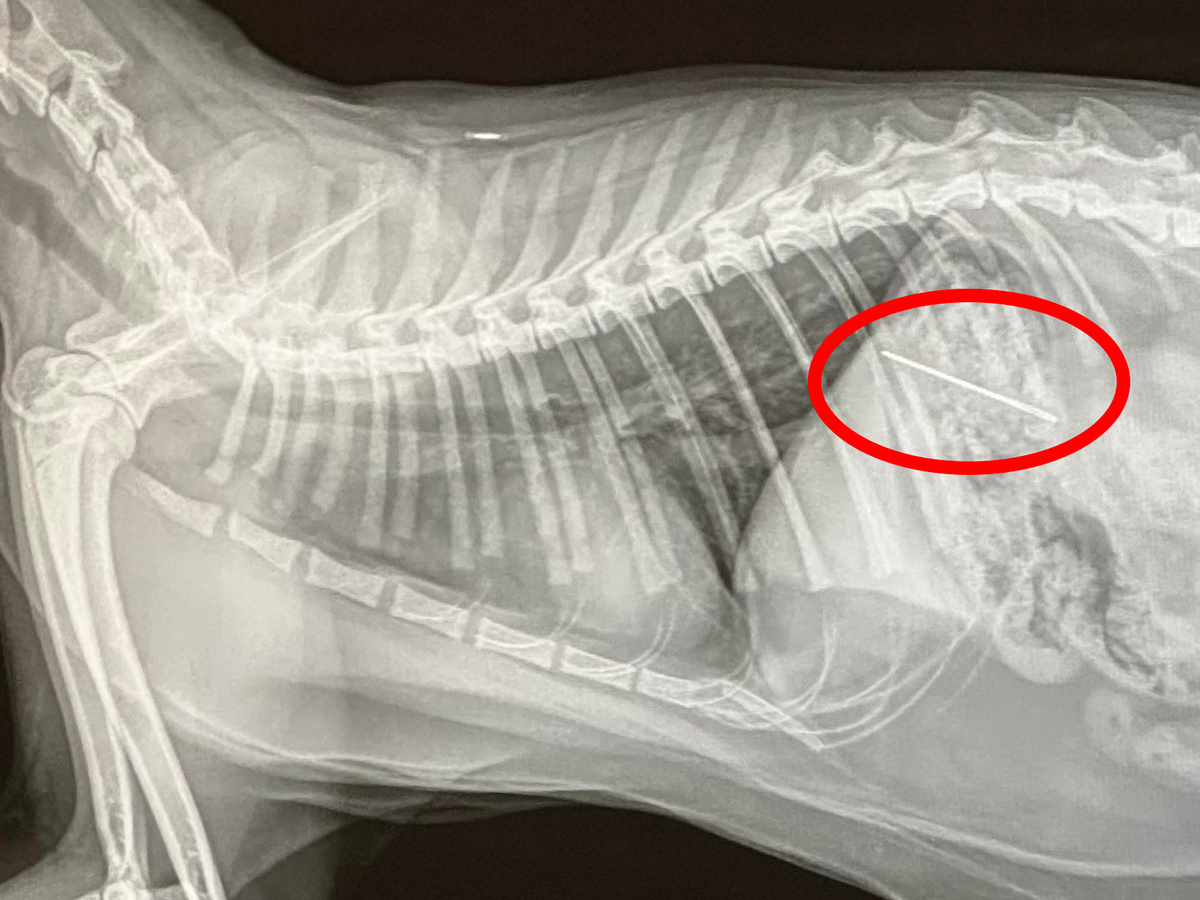

Hello. On Sunday March 30th, my cat Castiel, decided to break into my sewing kit and eat the thread... needle and all. Luckily, I saw it happen. I will never forget looking over and seeing the flash of the metal needle as it dangled from his mouth before disappearing. After a quick game of "catch the cat" I was able to rush him to the ER Vet. They took an X-Ray to confirm my story (I don't think they believed me) and sure enough a sewing needle was sitting pretty in his tummy. $4000 CAD later and a lot of tears on my part the vet managed to get the needle out using a magnet.